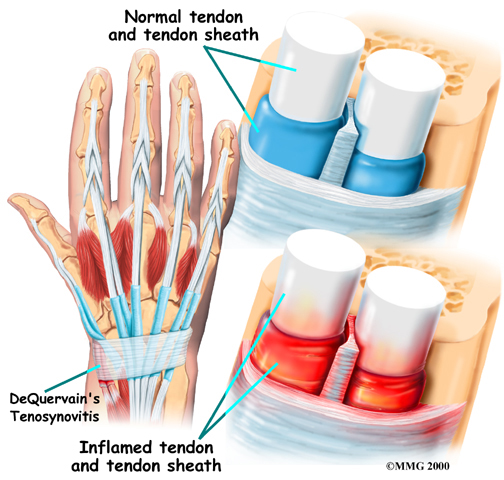

De Quervain's Disease and Trigger Finger

Tendon problems are also common in the hand and wrist. De Quervain's tenosynovitis is characterized by swelling and inflammation of tendons that attach the base of the thumb to the wrist. The tendon sheath also becomes irritated and this leads to pain in the wrist and thumb while moving the hand or grasping an object.

A similar issue is called stenosing tenosynovitis or trigger finger, in which the tendons that allow the fingers and thumb to bend and extend become inflamed. When this occurs, pain and stiffness may develop in the fingers. Eventually, it becomes increasingly difficult to move the fingers or thumb.

Related Document: Ari Levine PT, PC's Guide to Trigger Finger and Trigger Thumb